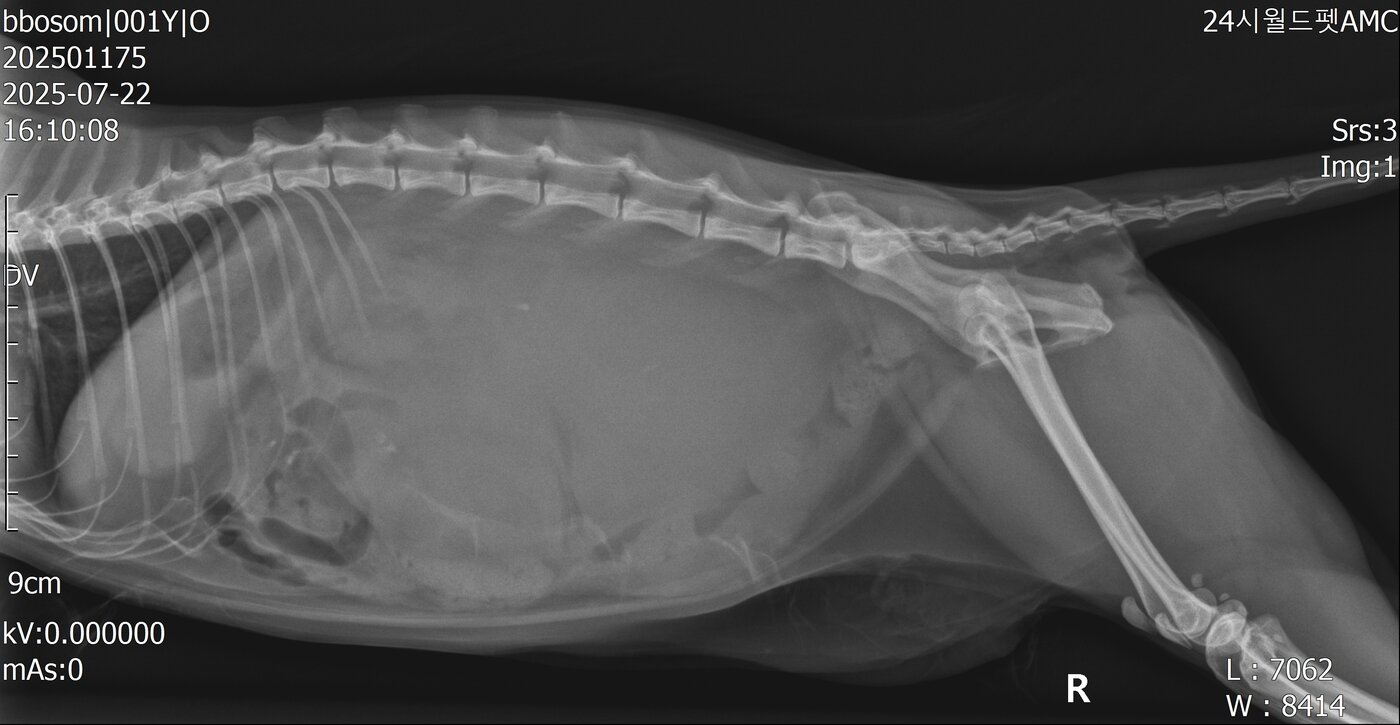

본문 이미지 - 뽀솜이는 신장 파열로 소변이 복강과 후복강까지 번져있던 상태였다(월드펫동물메디컬센터 제공). ⓒ 뉴스1

뽀솜이는 신장 파열로 소변이 복강과 후복강까지 번져있던 상태였다(월드펫동물메디컬센터 제공). ⓒ 뉴스1